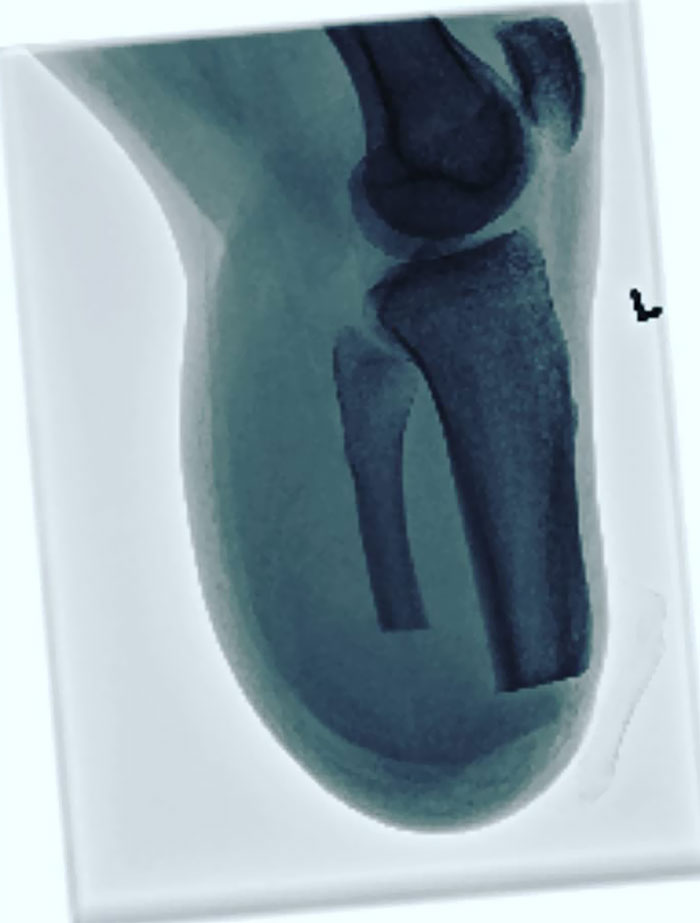

Ineffective Gold Thread Acupuncture Treatment For Osteoarthritis Of The Left Knee

Wait... Those squigly lines are gold threads? Can somebody please explain?